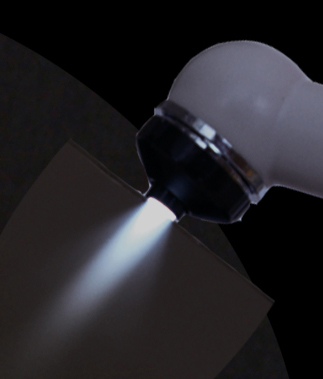

Fastest and most reliable curing light – FUSIONand Full accessories for fluorescent and transillumination oral exams; Two extra light heads: Violet and White light heads

DOE system uses high power LED illumination and high contrast switching filter for oral exam beyond normal visualization capabilities

• Small, Cordless, and Reliable

• Ease of access to detect unreacheable areas including the back throat

• No hair drier cooling fan noise

• Multi-wavellength LED illumination

• Always ready without sleeping mode